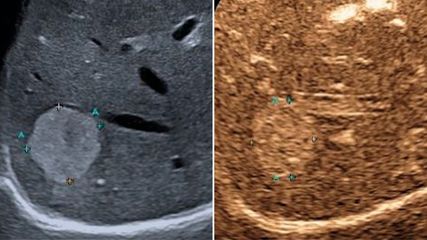

Ein 68-jähriger Mann stellte sich wegen wiederholter Stürze, bei denen er zeitweise das Bewusstsein verloren hat, an der Unfallambulanz vor. Beim Eintreffen in der Klinik wurde frisches Blut auf seiner Kleidung entdeckt. Aufgrund seines niedrigen Blutdrucks und seiner Vorgeschichte einer nutritiv-toxischen Leberzirrhose wurde er bei Verdacht auf Varizenblutung auf die Überwachungsstation verlegt. Dort erhielt er eine antibiotische Abschirmung und eine vasoaktive Therapie, bevor eine Gastroskopie in Intubationsnarkose durchgeführt wurde.

Hier zeigte sich in Inversion ein initial von einem Koagel bedecktes, großes, nicht aktiv blutendes Fundusvarizenkonglomerat (Abb. 1). Dieses wurde mit der Injektion von 5 Portionen Gewebekleber (2-Octyl-Cyanoacrylat) behandelt. Aufgrund der Größe der Varizen war eine komplette endoskopische Versorgung aber technisch kaum möglich, sodass ein transjugulärer intrahepatischer portosystemischer Shunt (TIPS) und eine interventionelle Embolisation der Varize empfohlen wurden. In der CT-Splenoportografie imponierte die Varize allerdings bereits ab dem Abgang von der Vena lienalis komplett durch den Gewebekleber verschlossen, sodass auf eine Embolisation verzichtet werden konnte.